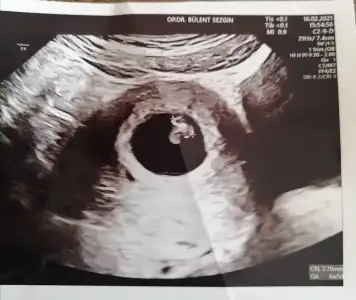

merhabalar yoldaslarm, belki hatirlarsiniz sizlerden opu ve transfer gunu dua istemistim, bgn transferimin 12.gunu degerim 626, aslinda daha once yzacaktm ama inanamadigimdan ve artisi gormek istedigimden yazamadim, 6.gun idrarda cikti, ayni gun kanda da 38ile basladim, bahsetmistm yumurta kalitem 4bc idi ve transferin ertesi gunu dusmustum, hic olacakmis gibi hissettmemistim, Allah bin kere razi olsn sizlerden, kulun kula duasi daha makbulmus, belki bir arkadasimin duasi kabul oldu.. cok cok sagolun